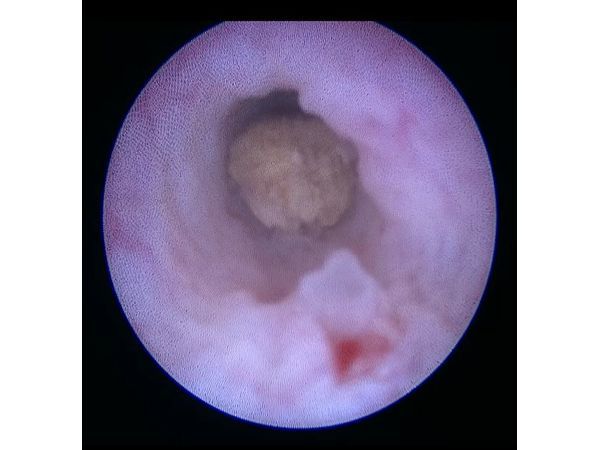

Уретероскоп проведён в левый мочеточник, на расстоянии 1 см от устья визуализирован конкремент жёлтого цвета с множеством граней, прилежащий к стенке, где отмечается отёк. Плотное образование удалено с использование корзинки. После удаления отмечена умеренная кровоточивость слизистой мочеточника в интрамуральном отделе в месте стояния конкремента. В левый мочеточник установлен Double-J стент, фиксирующая нить выведена через уретру наружу. Выполнена катетеризация мочевого пузыря.